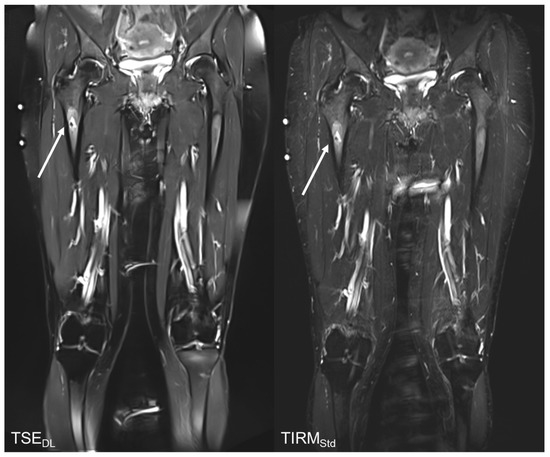

Reduction in Acquisition Time and Improvement in Image Quality in T2-Weighted MR Imaging of Musculoskeletal Tumors of the Extremities Using a Novel Deep Learning-Based Reconstruction Technique in a Turbo Spin Echo (TSE) Sequence

3.4. Qualitative Image Analysis